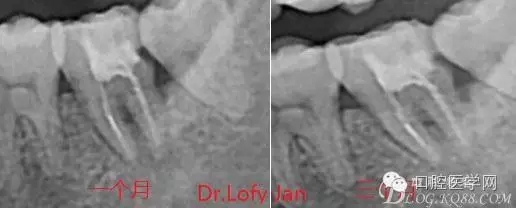

曲面斷層片在未試尖根管治療中的病例整理

前言:自己做的一些曲面斷層片在未試尖根管治療中的病例整理,發(fā)現(xiàn)問題很多包括自身的,技術(shù)的,還有設(shè)備的問題,予以總結(jié)整理并期待進(jìn)一步提高。

病例分析:曲面斷層片在x線輔助診斷與檢查中目前大多數(shù)文獻(xiàn)和著作都建議只能作為初診拍片檢查手段,不能作為終末疾病的確診與手術(shù)療效的評價(jià)指標(biāo),臨床大部分中小型門診都因?yàn)樵O(shè)備不齊全導(dǎo)致信息偏差很大。